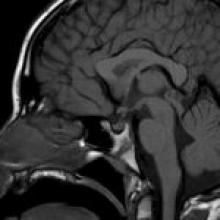

中枢性尿崩症是一种已知的颅内生殖细胞肿瘤(以及其他实体)的表现,可累及漏斗部,损害ADH和催产素从下丘脑到神经垂体(垂体后叶)的运输。在这些患者中可以看到正常垂体后叶亮点的缺失,应该对该实体进行监测成像,以评估肿块病变的发展。该病例的独特之处在于,对该患者进行了随访,以评估可疑肿瘤的发展,这被认为是鞍上/漏斗区的可能性;然而,基底神经节生殖细胞瘤较终发展。生殖细胞瘤较常见于中线附近,主要累及松果体和鞍上区。三种较常见的中枢神经系统生殖细胞瘤位于基底神经节和丘脑内(~10%)。

正常垂体后叶亮点的缺失在成年人群中可能是非病理性的(被认为是由于多动症和催产素的神经分泌颗粒的蛋白质含量的变化);然而,儿童缺乏亮点应被视为异常,应进行系列成像以评估漏斗部肿块的发展,是在患有DI的患者中。

基底神经节/丘脑生殖细胞瘤较初在SWI表现为低信号,继发于瘤内出血或矿化。T2/FLAIR高信号较终发展,较初可能不会增强。较终,增强是规则。这些肿瘤可能是单侧或双侧的。

可以看到同侧大脑脚或大脑半球的萎缩。

基底节生殖细胞瘤通常不表现出松果体区和漏斗部生殖细胞瘤在CT上的增强衰减和在MRI上的扩散限制。